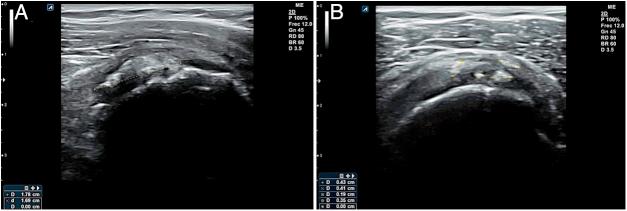

Musculoskeletal ultrasound (MSU) is a technique which has been extended to practically all medical specialties that comprise this pathology. Family Doctor (FD) has not been away from this process due to its great wide of competences, using it in different scenarios inside his common practice in which he can get profits in a reliable, efficient and effective way. Ultrasound equipment incorporation in Primary Care (PC) centers is an increasing reality, contributing to high ranges of accessibility, immediacy and clinic handle capability, and thus, together with the high prevalence in this area in locomotor apparatus, turns MSU into an strategic action for the improvement of the resolving capacity and consequently for the health care. To ensure proficiency among users, it's being necessary to define the benefits and potential risks its use can cause, as well as its different scenarios, avoiding unnecessary explorations and optimizing the investment of this resource at PC level. This paper pretends to summarize the state of the art of the musculoskeletal ultrasound and its benefits for the FD into this efficient and effective scenarios.

肌肉骨骼超声(MSU)是一种已被应用于几乎所有涉及该病理学的医学专业的技术。家庭医生(FD)因其广泛的能力范围也参与到了这一进程中,在其日常诊疗的不同场景中使用该技术,从而能够以可靠、高效且有效的方式从中获益。超声设备在基层医疗(PC)中心的应用日益普遍,这有助于提高可及性、即时性和临床处理能力,因此,鉴于运动系统在该领域的高患病率,肌肉骨骼超声成为提高诊断能力进而改善医疗保健的一项战略举措。为确保使用者的专业水平,有必要明确其使用可能带来的益处和潜在风险,以及不同的应用场景,避免不必要的检查,并在基层医疗层面优化该资源的投入。本文旨在总结肌肉骨骼超声的现状及其在这些高效有效场景中为家庭医生带来的益处。